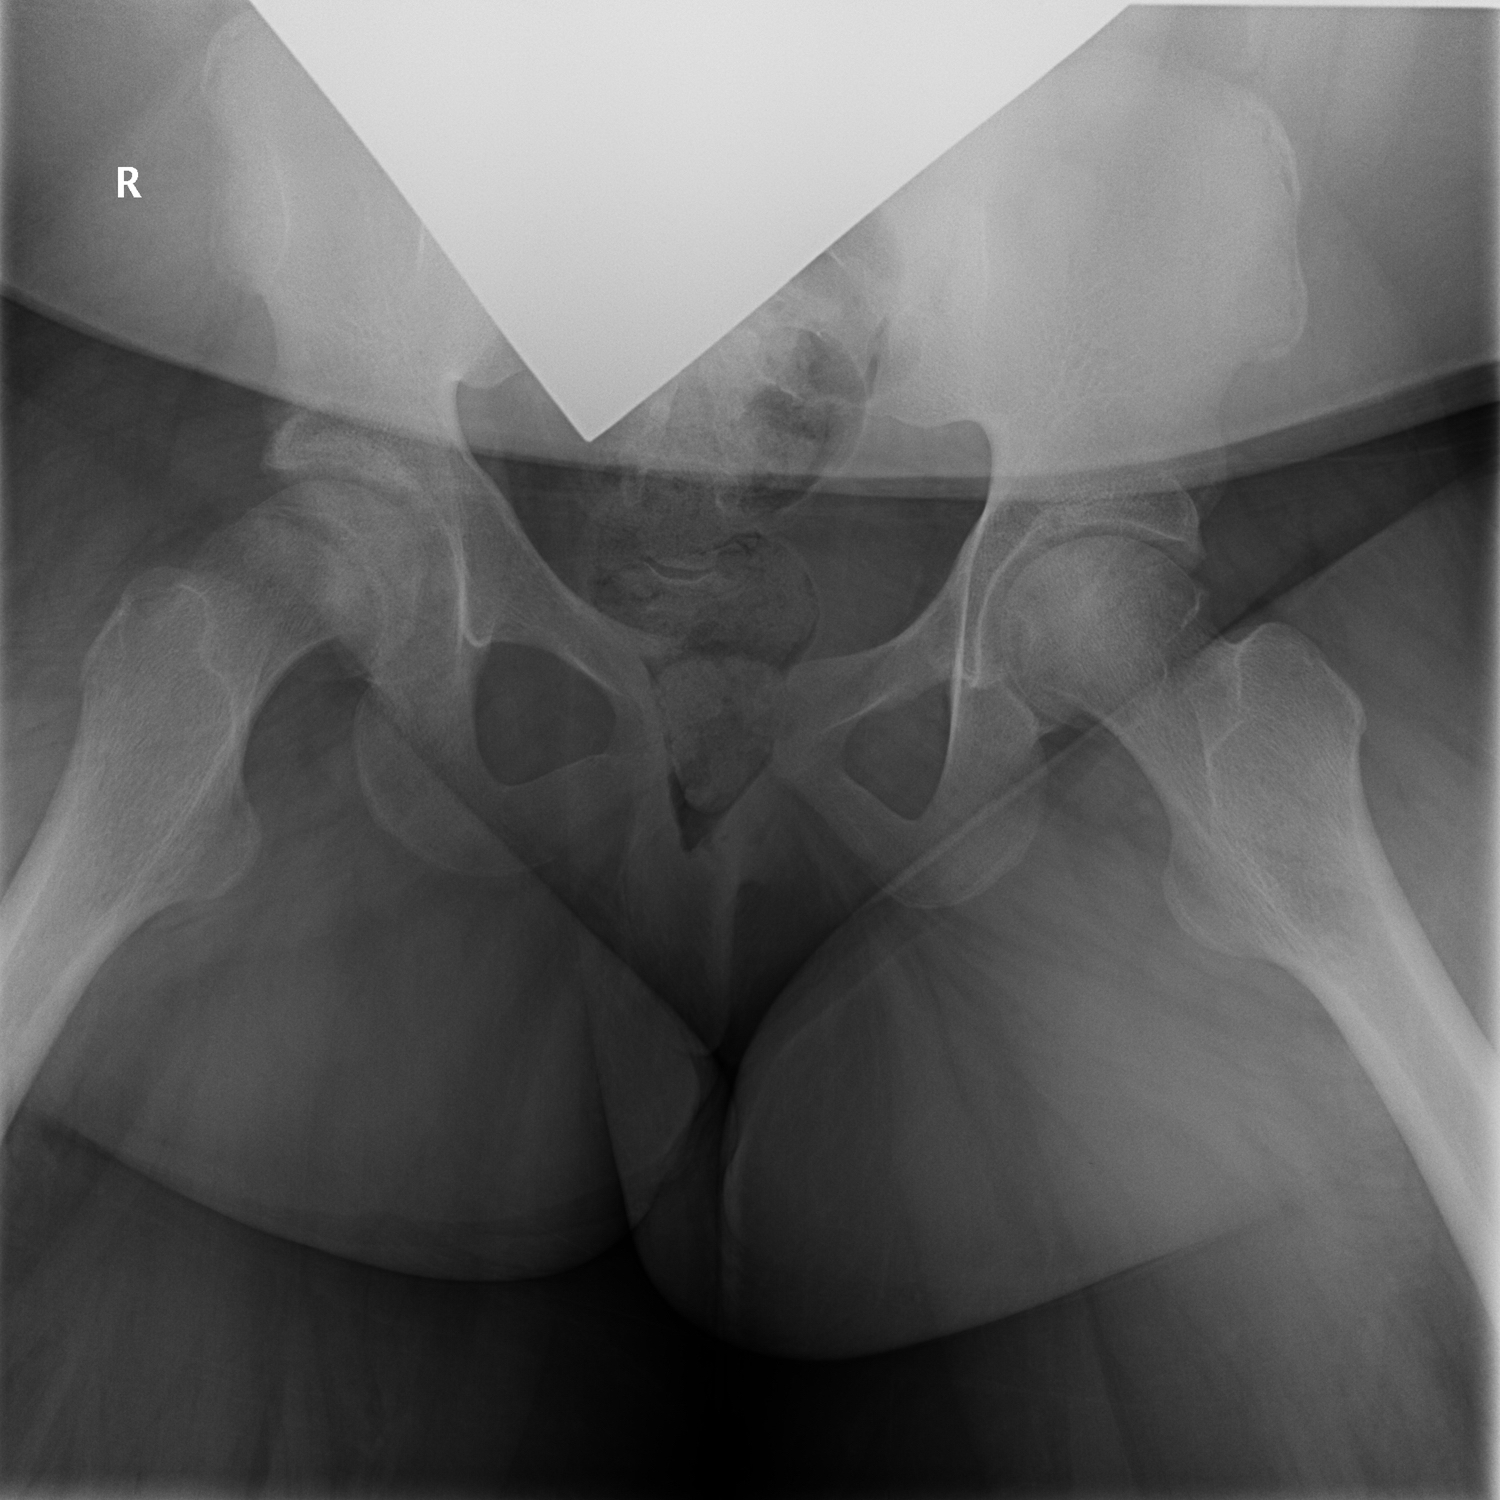

Upon presentation to the orthopedic clinic several months later, her chief concern was chronic right knee pain of 1 year’s duration. She was able to bear weight with crutches. Knee examination findings were unremarkable, but she experienced exquisite pain with log roll on the right lower extremity. AP and frog-leg lateral pelvis radiographs were taken, the latter of which is shown in Figure 1.

Figure 1. Radiographic scan of the pelvis.

AP and frog-leg lateral radiographs of the girl’s pelvis (Figure 1) revealed bilateral slipped capital femoral epiphysis (SCFE). Left-side findings suggested remote, healed SCFE, and right-side findings suggested acute versus subacute SCFE with an open physis. Her past medical history revealed obesity and hyperinsulinemia with evidence of insulin resistance.